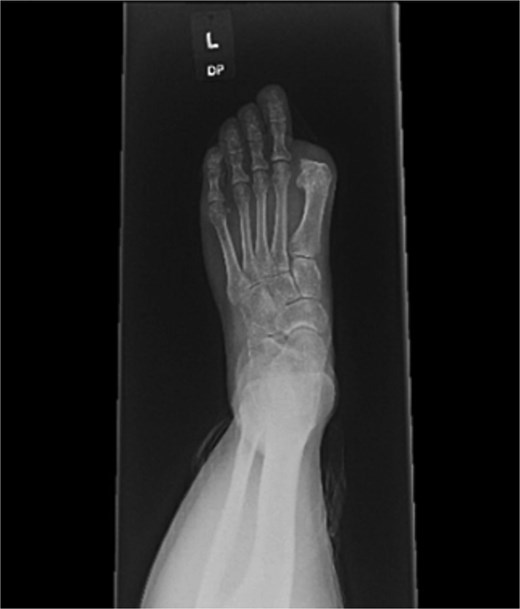

At 8 weeks, she underwent left hallux amputation at the MTP joint with removal of both screws, resection of nonviable tissue, and application of negative pressure wound therapy (NPWT) (Fig. 3). Intraoperative cultures demonstrated polymicrobial growth, including Pseudomonas aeruginosa and Staphylococcus aureus. She was treated with oral trimethoprim–sulfamethoxazole based on susceptibilities and infectious disease recommendations, with continued NPWT. The wound healed uneventfully, and she returned to full activity. Following wound healing, she was fitted with a custom great toe prosthetic device (Fig. 4). At 1 year, she reported no pain and had resumed gym workouts without limitation. Clinical examination showed good prosthetic function (Fig. 5), and radiographs demonstrated satisfactory healing (Fig. 6).

Gross specimen of amputated hallux (left) and postoperative radiograph following metatarsophalangeal joint amputation and screw removal.